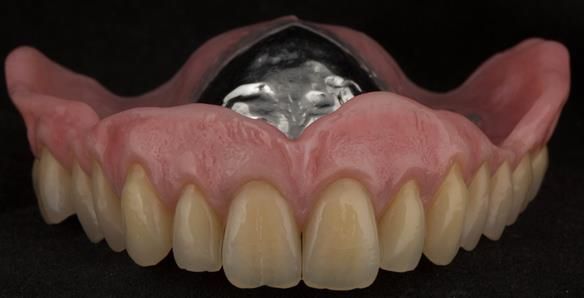

- Definitive dentures (Mk 2) – complete upper metal reinforced and lower cobalt chromium based partial of hygienic Scandinavian design to be made 9 - 12 months after extractions of all upper teeth and LR5 and LL4

The clinical situation and treatment process is shown in detail below with photographs.

The patient has been successfully rehabilitated and is now having periodontal maintenance from Syed Abad, Specialist in Periodontics at the practice. His quality of life has improved considerably. The clinical prosthodontics was provided by me and the technical work by Rowan.